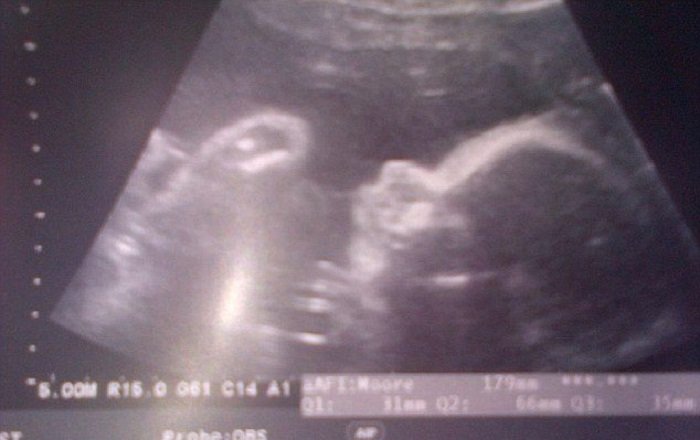

В это время Элисон заботилась о недавно родившейся внучке и совсем не ожидала новости о собственной беременности. «Я бабушка, у меня 26 лет не было месячных, я попросту не могу быть беременной!» — проронила обескураженная женщина, рассматривая снимки УЗИ.

Ей казалось, что медики спутали снимки, но после долгих убеждений Элисон поверила словам врачей. О своей беременности женщина узнала всего за 8 недель до рождения ребенка!